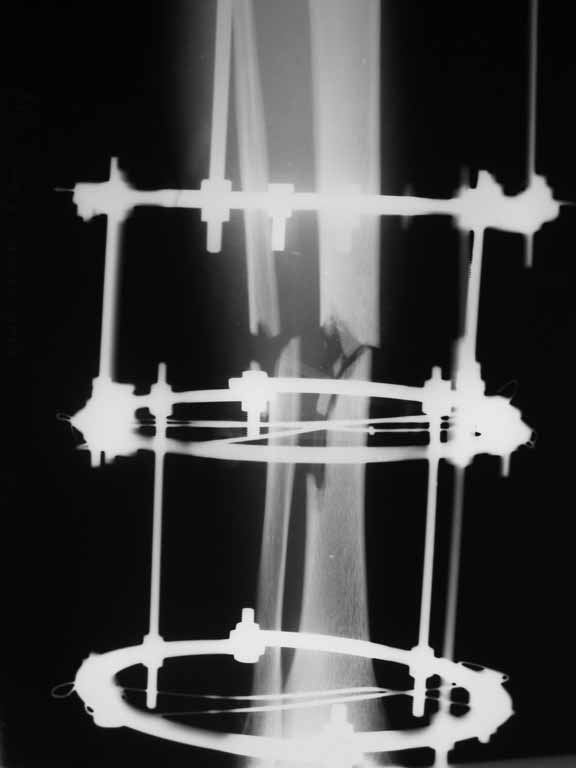

Re: Перелом большеберцовой кости с дефектом дифизарной части

Извините, не загрузились сразу все рентгенограммы.